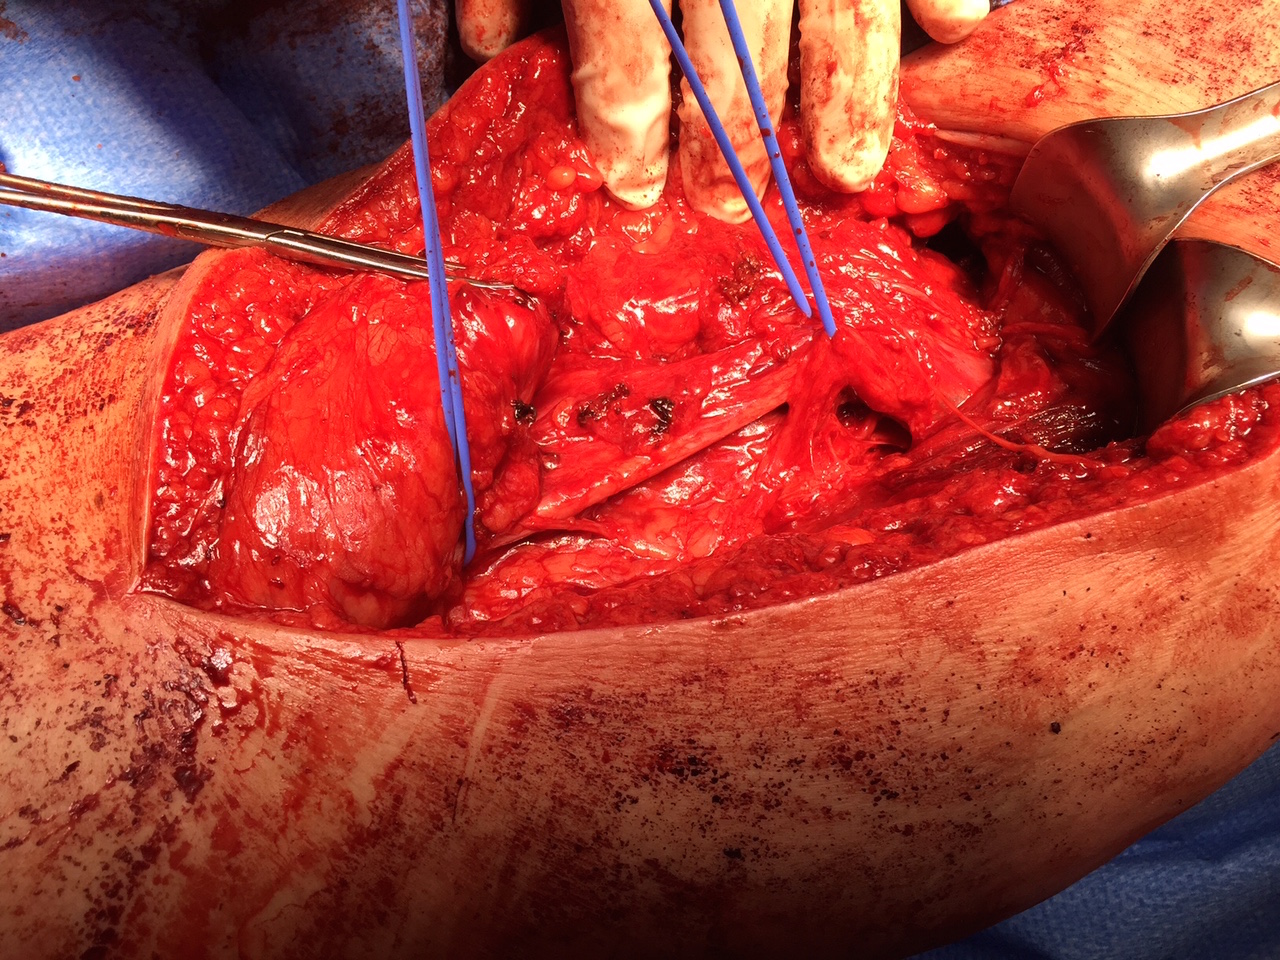

Expose ischial tuberosity

- superior retractor on ischial tuberosity

- medial and lateral retractors, care with sciatic nerve

- use osteotomes to create bleeding

- 2 - 3 suture anchors, double loaded

Exposing ischial tuberosity (*) with Cobb retractor